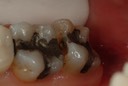

Wayne Chin #31 amalgam removal